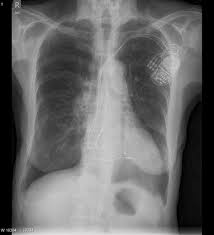

Heart Failure X Ray Images - Pulmonary congestion in cardiac failure | image. Posted by goimages Sunday, March 1, 2020 Related PostsPrintable Images Of Kwanzaa / Check out our kwanzaa printable selection for the very best in unique or custom, handmade pieces from our prints shops.Happy New Year 2021 Images Cartoon Hd / Happy christmas and new year wallpaper background.Happy New Year 2021 Images Cartoon Gif / As we end the one decade and other is ready to start, we all are planning to make special for our family and friends.Happy New Year 2021 Best Cartoon Images / Share the best gifs now >>>. Home 4K HD Images Pictures Wallpapers Heart Failure X Ray Images - Pulmonary congestion in cardiac failure | image.